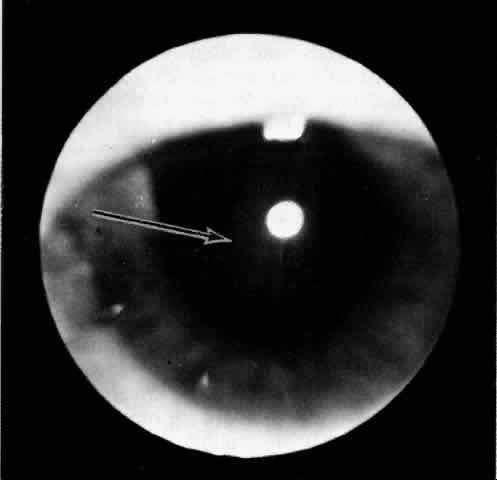

Fig. 2. The ora serrata is visible in the pupillary space due to a ciliochoroidal effusion that developed after retinal detachment surgery in an aphakic eye. The arrow indicates the ora bay. (Courtesy of Retina Service, Wills Eye Hospital, Philadelphia)

Fig. 5. Flat ciliochoroidal effusion. The ora serrata is visible without scleral depression in a patient with Schepens-Brockhurst syndrome. The arrow indicates the ora bay.